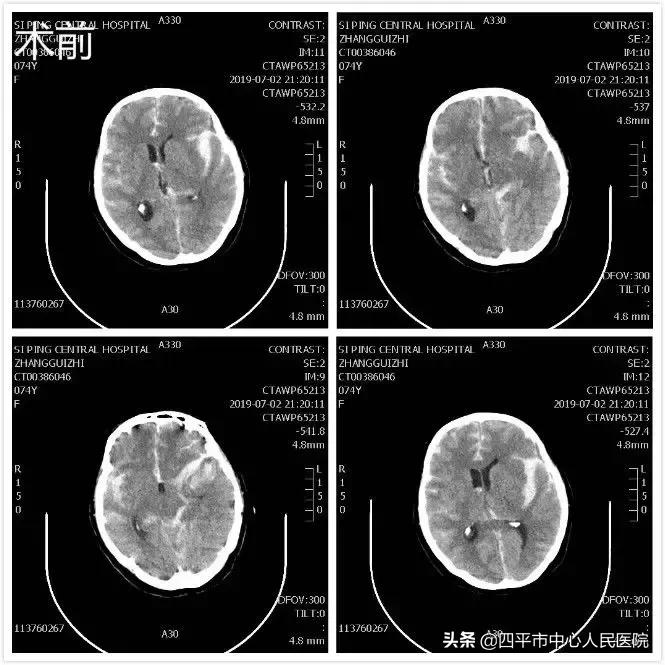

患者张XX,于入院前2小时突发神志不清,伴恶心呕吐,呕吐物为胃内容物,四肢不动,伴尿*禁失**,无抽搐。由家属送至梨树县医院,行头CT检查提示脑出血,为求进一步治疗转送至我院,我院神经内科给予复查头CT提示大量蛛网膜下腔出血,首先颅内动脉瘤破裂所致,由于患者到我院时深度昏迷状态,呼吸微弱,HUNT-HESS分级5级,不适合行头部CTA检查及介入栓塞治疗,家属强烈要求手术治疗,请麻醉科行气管插管后入手术室,李晓东主任带领马龙急诊全麻下经左侧扩大翼点入路行右侧脑室外引流术及颅内动脉瘤探查术,术中探查患者左侧后交通动脉巨大瘤,临时阻断颈内动脉后给予确切夹闭,术中动脉瘤没再次有破裂出血。术后第1天,患者呈浅昏迷状态,刺痛可定位,四肢可自主活动。复查头部CT满意,查头部CTA见左侧后交通动脉瘤夹闭确切。但患者于术后第3天,出现迟发性脑内血肿,考虑到预后不好,家属放弃治疗出院,临出院时对我科李晓东主任及马龙医生的积极救治表示感谢。